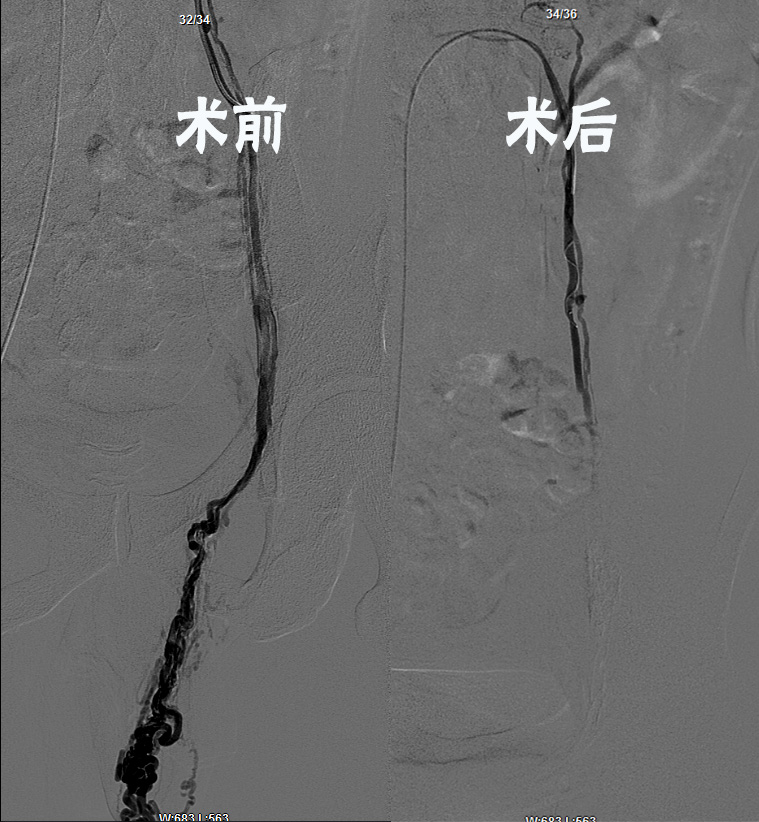

46岁的张先生左侧精索静脉曲张7年、阴囊坠胀感加重3年,严重影响正常生活,在多家医院诊断为重度精索静脉曲张,建议行常规手术或腹腔镜手术治疗。患者为免受开刀之苦,由外地慕名来到我院介入血管外科就诊。王立军主任仔细查看患者情况,发现其左侧阴囊较右侧大近一倍,做吸气、鼓肚子动作时阴囊可见曲张静脉,诊断明确,决定采用经皮介入精索静脉泡沫硬化栓塞术进行治疗。精索静脉的介入栓塞术是真正的零切口,术后6-8小时就能下地活动,第二天阴囊坠胀感明显缓解,不仅为患者解决了痛苦,且大大降低了花费。

王立军主任介绍,介入血管外科掌握成熟的血管介入操作技术,积累了丰富的血管内介入诊疗经验。开展的经皮精索静脉泡沫硬化剂栓塞术与传统的外科手术相比,创伤小(无刀口)、见效快、疗效确切、恢复快、住院时间短、花费低。该技术同样可治疗女性的盆腔静脉瘀血综合症,该综合症也是引起痛经和女性不孕症的重要因素之一。